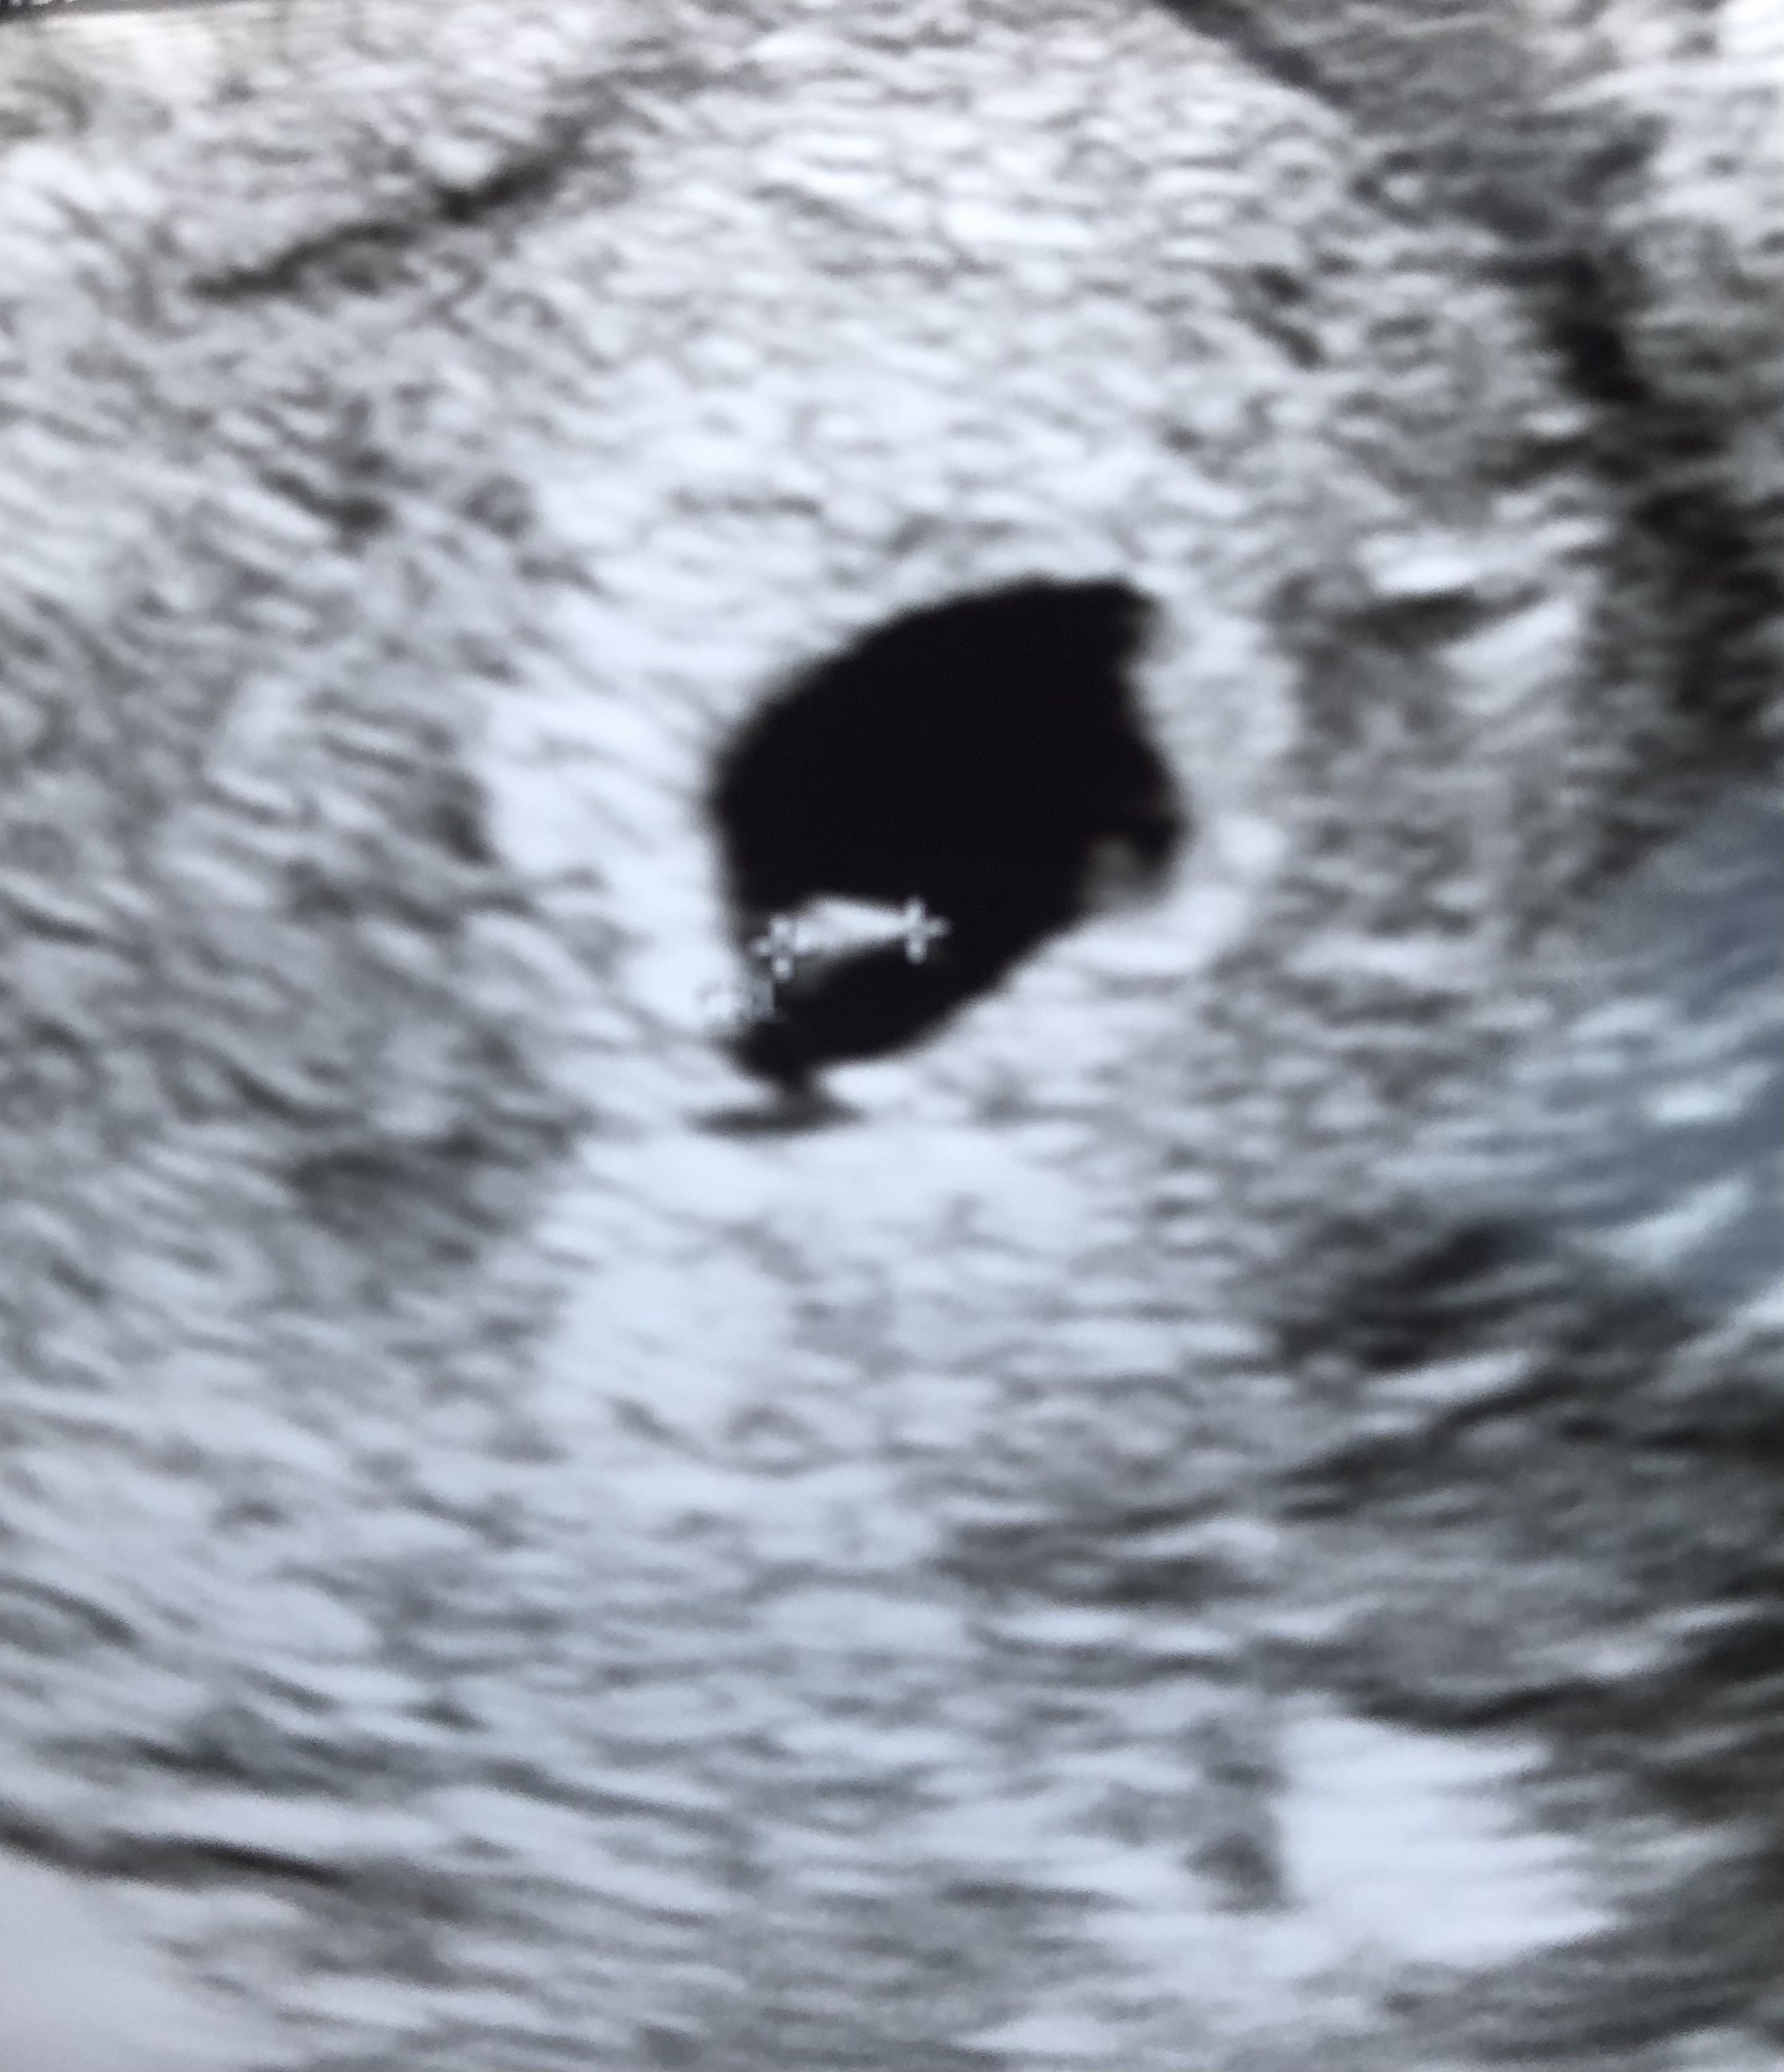

Jestem już po! Okazało sie, ze z mojej ostatniej miesiaczki wychodzi 6tydzień, ale z racji mojej późnej owulacji, ciąża jest +/- tydzien młodsza, kolejna wizyta za tydzień. L4 dostałam bezproblemowo. :)

Lekarz zrobił nawet hcg, wyszło prawie 5tys! :)

Zarodeczek jest ❤️

• 8D3A5D93-6A41-4D98-9750-FAFFD2B9AD21.jpeg

8D3A5D93-6A41-4D98-9750-FAFFD2B9AD21.jpeg

1 MB · Wyświetleń: 76